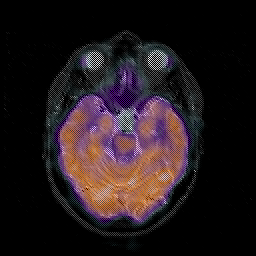

Glioblastoma multiforme overlay -- Slice #20

[Home][Help][Clinical][Tour 1][Tour 2][Tour 3] Slice 20